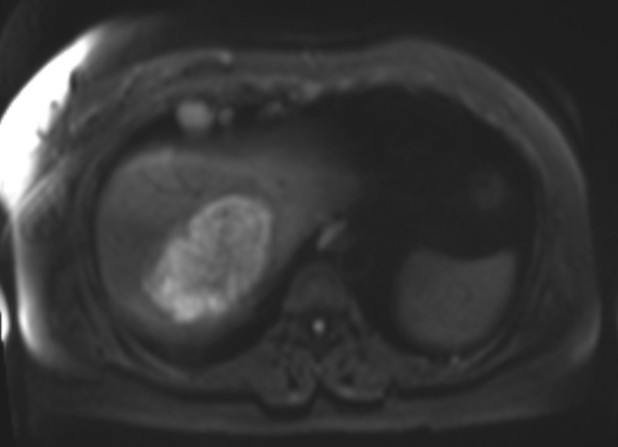

•Pre and post-contrast T1 fat saturation images: predominately T1 hypointense mass with areas of intrinsic enhancement. Answer: Intraductal papillary neoplasm of the bile duct (IPNB)

Axial diffusion weighted imaging: mass and filling defects demonstrate hyperintense signal on high B value diffusion imaging •MRCP and axial T2 fat saturation: diffuse intrahepatic biliary duct dilation; axial T2 fat saturation images confirm HASTE findings.

•Axial and coronal T2WI (HASTE sequences): An ~9cm hepatic mass with heterogenous, but predominately hyperintense signal, on T2WI. Associated intrahepatic biliary duct dilation with multiple curvilinear hypointense striations/filling defects.